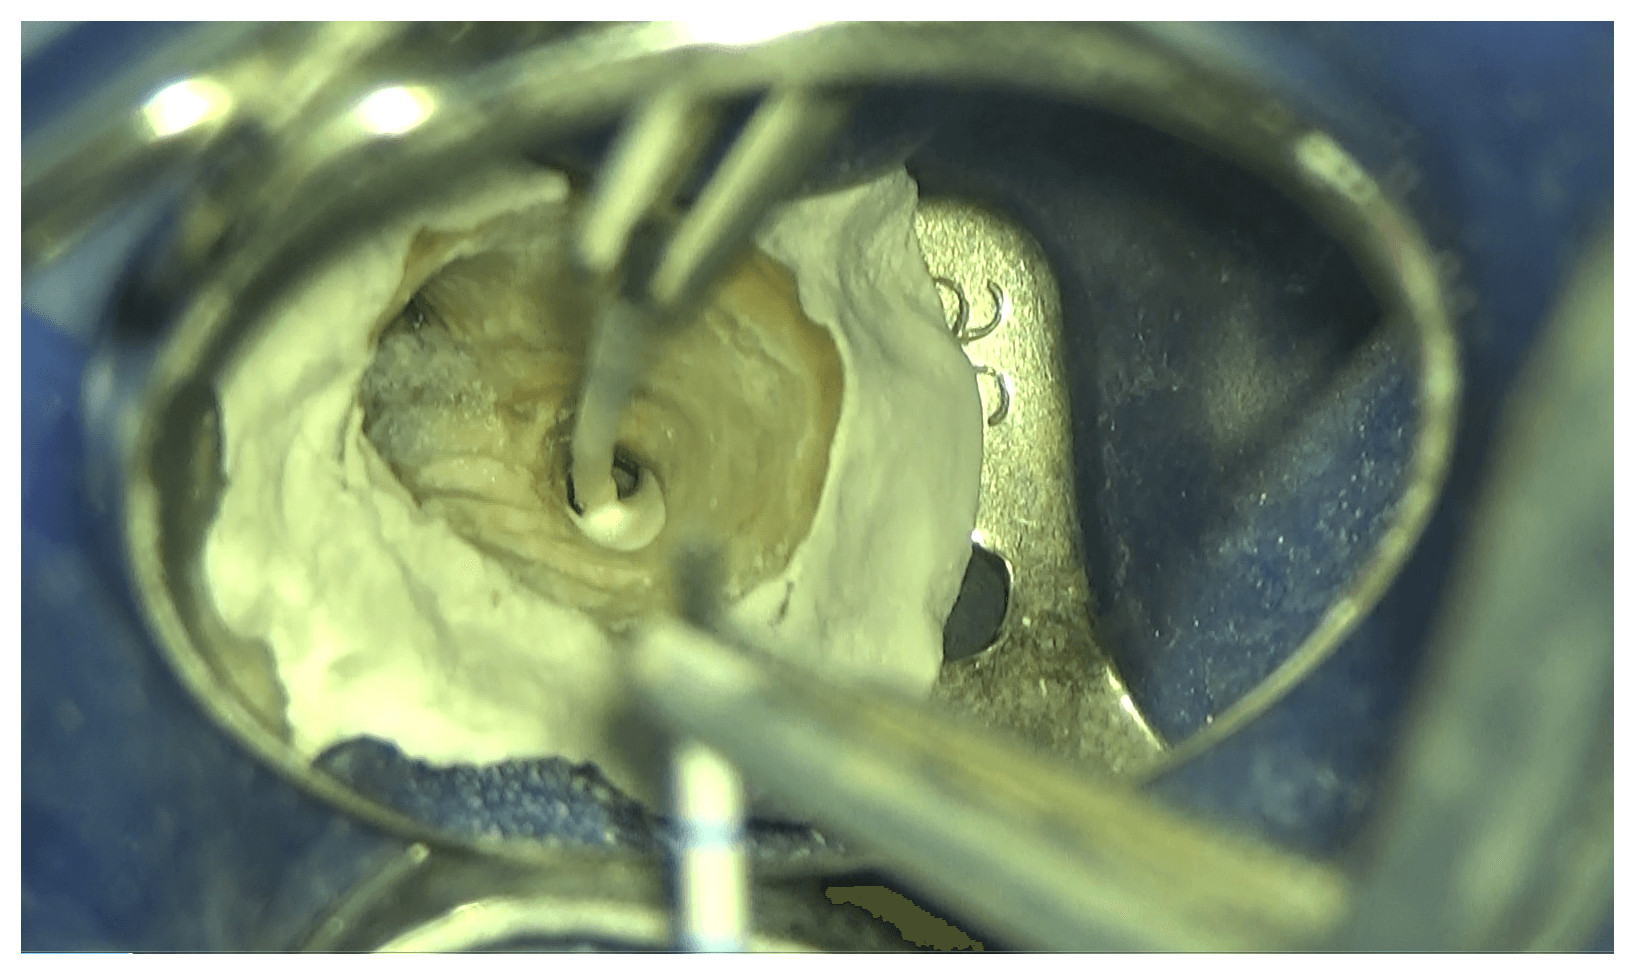

洗浄後、乾燥した状態です。

排膿や滲出液などもみられないので、この後根管充填処置(封鎖)を行いました。